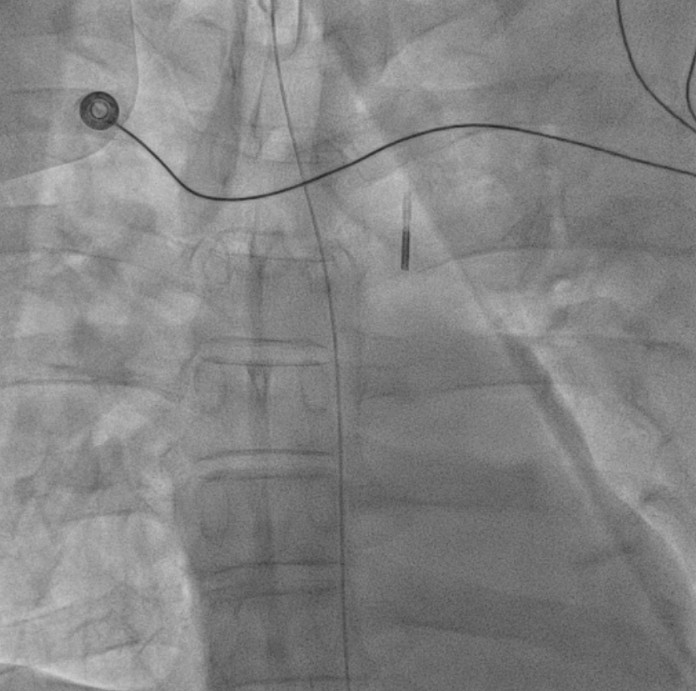

Staged PCI (Mar 6): One DES was placed in the LCX and one DCB in the LM–LCX segment. ECMO and IABP were successfully removed on March 8. Continuous renal replacement therapy was started for acute kidney injury. Brain CT showed watershed infarcts and a small subarachnoid hemorrhage, followed by gradual neurological recovery.

Transcatheter Edge-to-Edge Repair (Mar 27): TEE demonstrated severe mitral regurgitation with low cardiac output (~2 L/min). Two G4 XTW MitraClips were implanted successfully, improving hemodynamics.

Staged LM–LAD PCI (Apr 18): Two DES were deployed in the LM–LAD under mechanical and pharmacologic support.